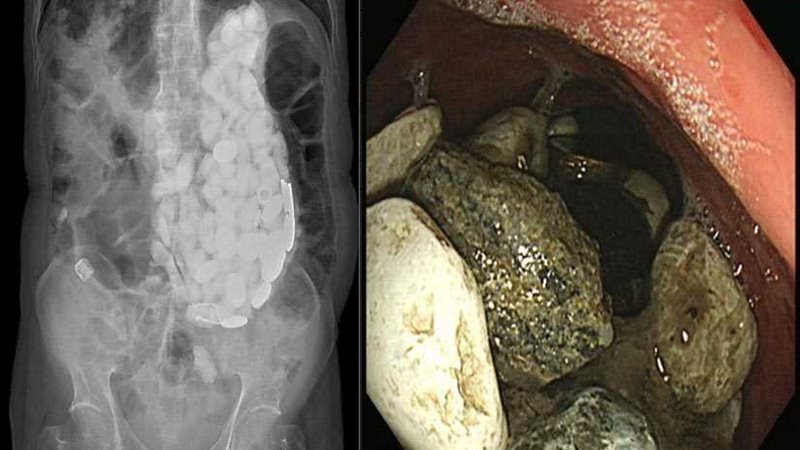

وخضع المريض لإجراء عدد من التحليل والاشعات لمعرفة سبب الأعراض المؤلمة التي يعانى منها.

لاحظ الأطباء المتخصصين أنهم يشعرون بشيء يشبه الحجارة الصغيرة عندما يلمسون بطن المريض.

وكشف الفحص بعد ذلك عن تراكم ضخم للأجسام "التي تحتل المعدة بأكملها" للمريض.

لكن الممرضات اللواتي صعقن تماما عندما عثرن على كتلة تحتوي على عشرات الأجسام الغربية، حيث تم استخراج كمية من الحجارة وأغطية زجاجات وقطع عملات معدنية تزن 2كيلوجرام ببطن المريض.

في البداية حاول الجراحون إزالة الأحجار وأغطية الزجاج وغيرها من داخل معدته باستخدام منظار حيث يتم إدخال أنبوب رفيع في المعدة من خلال الفم لكنهم فشلوا بسبب الكمية الهائلة من الأشياء التي كانت موجودة.